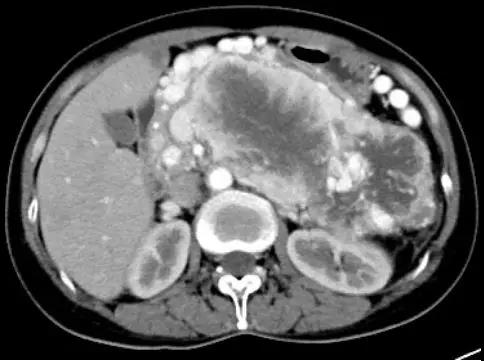

術(shù)前CT圖像

術(shù)前CT顯示患者腫瘤巨大,與脾臟、胰腺、胃、腎上腺、結(jié)腸界限不清,并且腫瘤合并局限性門靜脈高壓癥,被曲張的血管包繞,手術(shù)難度極高,風(fēng)險較大,腫瘤切除過程中稍有偏差就會損傷密布叢生的血管,很可能發(fā)生術(shù)中致命性大出血。